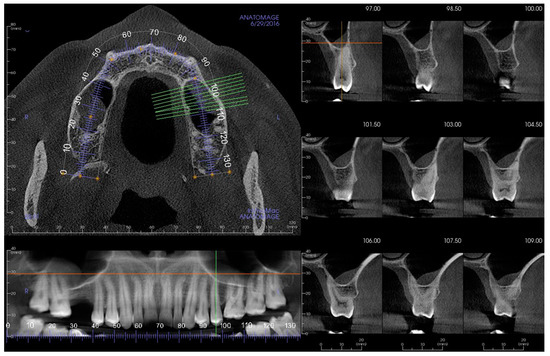

2. Materials and Methods